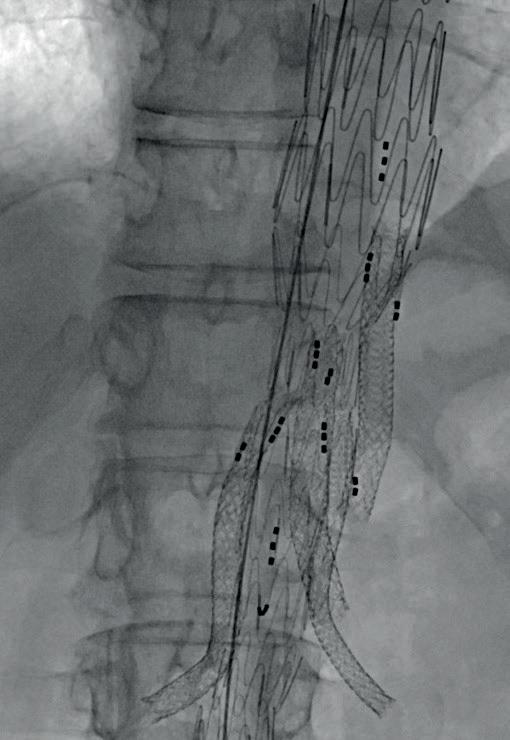

Recently conducted first-in-human procedures with a longer length of Bentley’s BeGraft Plus mark the latest in a series of moves from the company towards providing a dedicated bridging stent portfolio for fenestrated and branched endovascular aneurysm repair (FEVAR and BEVAR).

ERIC VERHOEVEN (PARACELSUS MEDICAL University and General Hospital, Nuremberg, Germany), who conducted the procedures, speaks to Vascular News to share his expert insights on the topic. He comments on the development of Bentley’s complex aortic offering from general to dedicated solutions that are “easier to use” for aortic specialists and “more effective” for patients.

The evolution of complex aortic care

Setting the scene, Verhoeven highlights the long and winding evolution of complex aortic intervention towards fenestrated and branched repair. Over the past 25 years, he says, a multitude of new stent designs and concepts have emerged with varying levels of success. Part of the challenge has been meeting the different requirements for bridging stents in both FEVAR and BEVAR, Verhoeven notes, stressing the importance of having dedicated products—rather than adapted ones—for different anatomies and clinical scenarios.

therefore requires different tools.

A need for dedicated stents

Verhoeven cites Bentley as the first company to understand the clinical need for dedicated bridging stents in FEVAR and BEVAR. He notes that, to date, the company has achieved on-label indications for the BeGraft and BeFlared in FEVAR and the BeGraft Plus in BEVAR, with the BeFlared emerging as the first dedicated stent for FEVAR and the longer BeGraft Plus, a dedicated stent in BEVAR.

Eric Verhoeven

While fenestrations are used mainly in complex abdominal aneurysms, Verhoeven elaborates, branches are adopted predominantly for thoracoabdominal aneurysms. “It’s therefore very important to understand that we need different stents,” he says.

In FEVAR, for example, Verhoeven notes that a balloon-expandable stent graft is needed due to its ability to flare and adapt to the fenestration, as well as its association with precise deployment. With BEVAR, on the other hand, both self- and balloonexpandable stents have the potential to be suitable options, with the choice depending on several factors. It is important with BEVAR to select a stent that “adapts to the situation”, Verhoeven says, noting how this can differ greatly from case to case. “Sometimes you need flexibility at different levels, sometimes you need radial force or kink resistance,” he continues, stating that the “ballgame in branched EVAR is more complex than the one in fenestrated EVAR” and

Verhoeven highlights in particular the success of the BeFlared in having achieved—in his opinion—the “ultimate goal” of a dedicated stent for fenestrations. He lists certain advantages of the BeGraft in fenestrations, including its availability in a wide range of diameters and lengths, its 6Fr compatibility, and its visibility due to a cobalt chromium stent design. On the BeFlared as a dedicated product in fenestrations, he underscores the benefits of a shorter procedure time (several minutes per target vessel), shorter fluoroscopy time (roughly one minute per

We will certainly, as users, benefit from these dedicated stents.”

target vessel), and—most importantly—easier precise positioning and the avoidance of “costly” mistakes.1

In branches, however, Verhoeven believes there is “potential for development” to find the “ideal” dedicated stent. “Will we ever have the ideal stent?” he queries, citing the need for case-dependent features as grounds for caution in seeking the perfect device.

Verhoeven’s caution rests on there being “really two or three stent designs that can be used [for BEVAR] in the correct anatomy”. By way of example, he explains: “If you work in a very narrow aorta, but there is still enough room for the branch, then you

want a bridging stent graft with the highest radial force; if you have a lot of room, that radial force is less important, but maybe kink resistance is more important and maybe flexibility at the distal landing zone to avoid kinking in the target vessel is important. “In branches, the requirements for the bridging stent are far more dependent on the anatomy. This complexity will make it difficult to build a stent that answers all requirements for all anatomies.”

Despite his reservations about the concept of an “ideal” bridging stent for BEVAR, Verhoeven expresses his confidence in the BeGraft Plus for use in this anatomy. “I think the BeGraft Plus was a very smart move,” he says.

In particular, Verhoeven points out the concurrent high radial force and kink resistance of the device, making it well suited to a broad range of BEVAR cases. “It may not fulfil all of my desires,” he comments, “but it has a very strong case to be used in branches.”

The BeGraft Plus is now on label for BEVAR, with Verhoeven having conducted the first-inhuman cases using the novel additional (longer) stent lengths of 77/78mm on 3 and 4 December at his centre in Nuremberg. Verhoeven reports that the device “worked very well” in the two cases. “We were certainly happy to have the longer BeGraft Plus, especially in emergency or off-the-shelf procedures to bridge long distances with its minimal foreshortening,” he comments.